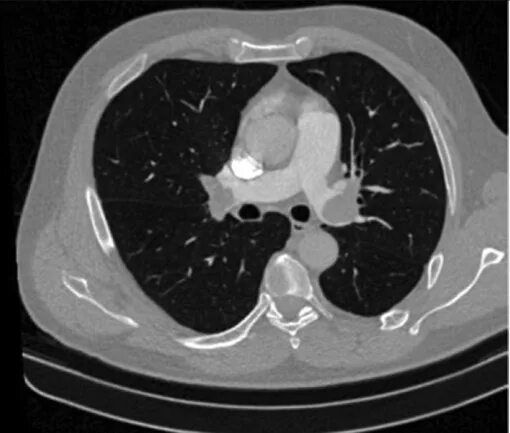

Ммрт